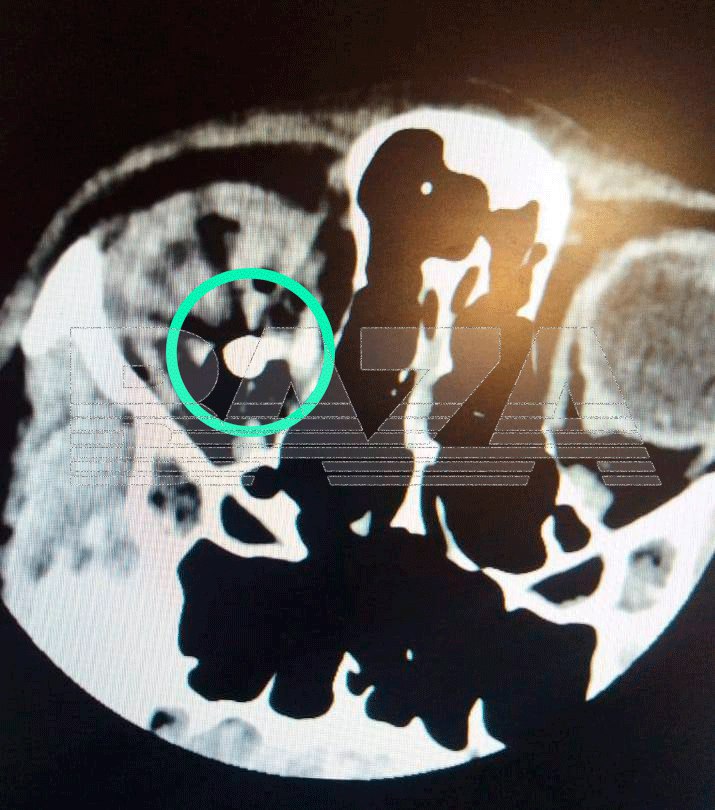

По данным «Базы», двое друзей играли с пневматическим пистолетом, но их забава переросла в ссору, и дело закончилось перестрелкой. В ходе конфликта один из подростков попал другому в глаз, после чего пуля прошла насквозь и застряла у пострадавшего в голове. Мальчика доставили в уфимскую клинику, но извлечь пулю врачи не могут до сих пор — она засела внутри на глубине 7 миллиметров. Родители уже написали заявление в полицию.